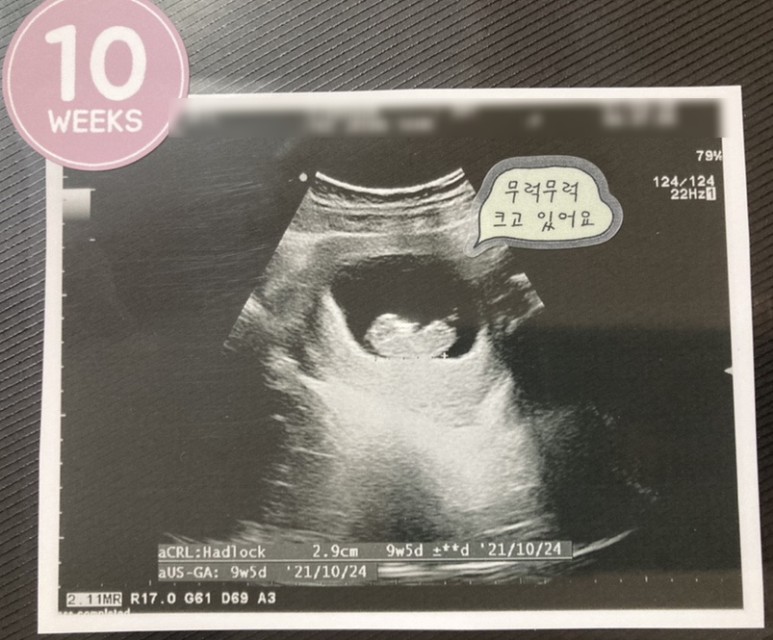

+ 초음파 – 진료비 8,400원 10주차. 밤에만 심한 입덧.

10w0d :: 2.9cm 예정일이 또 조금 밀렸네 그러나 크게 걱정할 일은 아니라고 한다.입덧은 나아졌지만 완전히 사라진건 아닌 애매한 컨디션!! 퇴근해서 집에 오면 시작된다.그래도 10주차가 되면서 식사량도 조금씩 늘었고 점심에 직원들과 맛있는 것도 먹으면서 하루 한끼는 맛있는 것도 먹고 잘 버틸 수 있었다.9주차에 입덧이 줄어든 뒤부터 복통이 심해졌지만 10주차에 그것도 적응했는지 가끔 따끔거리는 것 외에는 신경 쓰이지 않았다.+ 초음파 – 진료비 35,300원 11주차. 조금씩 줄어들고 있는 입덧과 복통 증세